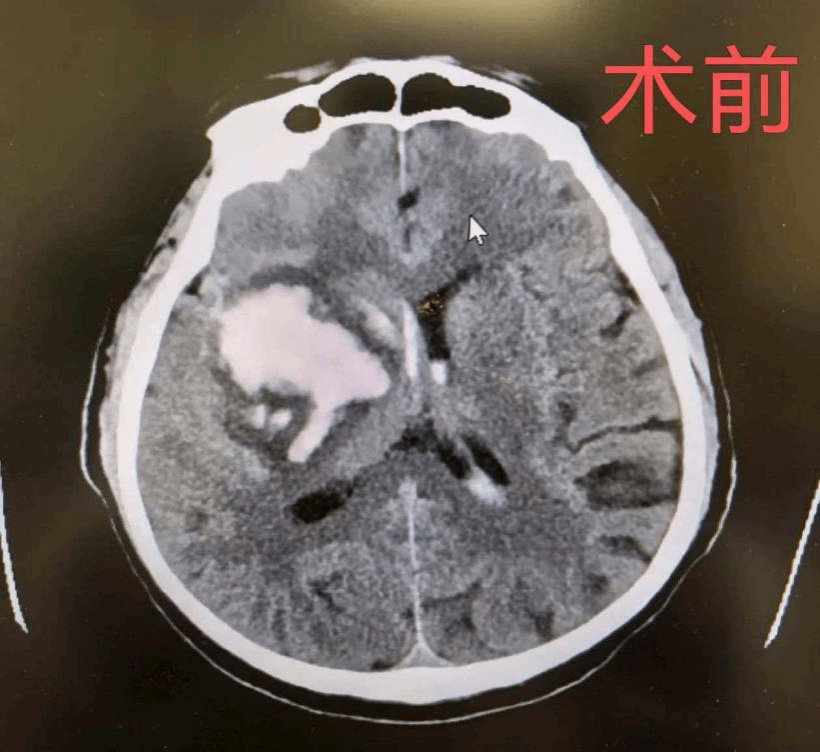

68岁陈大爷因突发肢体活动不灵、意识模糊紧急入院,头颅CT检查提示右侧基底节区脑出血,脑组织受压明显,中线结构移位,随时有发生脑疝、危及生命的风险。

术前CT显示,右侧基底节区可见大片高密度出血灶,血肿体积大,对周围正常脑组织造成显著压迫,是典型的高血压性脑出血表现,需立即手术干预。